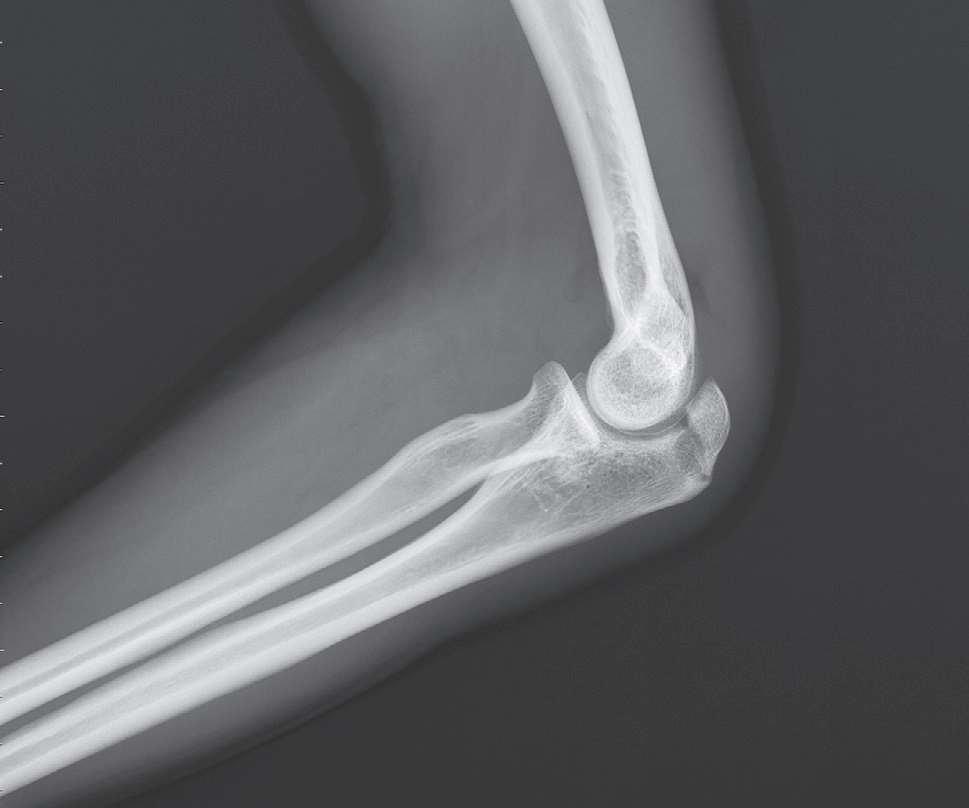

3.影像学检查(图8-1)。

图8-1 尺骨鹰嘴骨折X线片